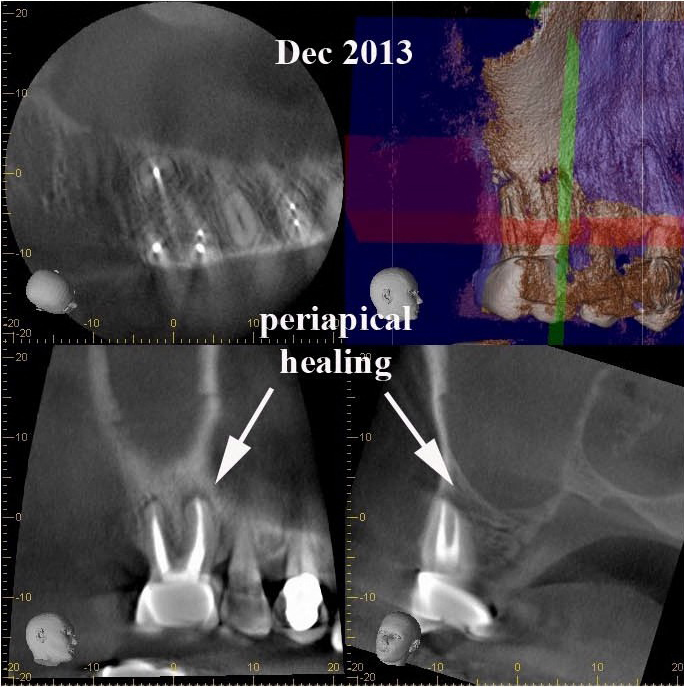

6 month recall following endodontic retreatment shows healing of the PARL.

After 6 months, extraction of tooth #2 and retreatment of tooth #3 has shown periapical healing.  The potential odontogenic source of the sinus infection has been eliminated.  Since the Mx sinus continues to show opacification, the patient is referred back to Dr. Haegen for continued sinus evaluation and treatment.